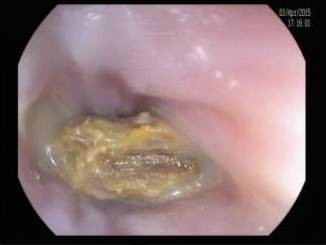

过去的两周内,西安交大二院内镜室接诊了14例上消化道异物患者,他们中年龄最大者80余岁,最小者才10岁,造成他们痛苦的罪魁祸首竟然都是枣核。生活中我们经常碰见鱼刺、肉骨头、假牙等卡在食管或是小儿误吞异物(硬币、发卡等)事件,医学上称为上消化道异物。在内镜检查和治疗开展以前,传统的处理方法是紧急外科剖腹或开胸手术取出异物或口服某些食物促使异物自然排出,但以上方法危险性大、并发症多、患者痛苦。随着内镜技术的进展和设备的普及,内镜下消化道异物取出术已经成为一门成熟的治疗技术,

交大二院消化内镜室已成功地为众多的上消化道异物的患者解除了痛苦.虽然经常加班加点,但看着患者担惊害怕地走进胃镜室,高高兴兴地走出胃镜室,再晚再累他们也觉得欣慰.